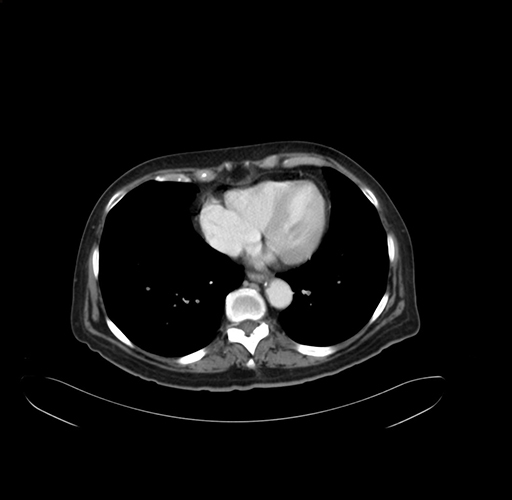

Axial Venous